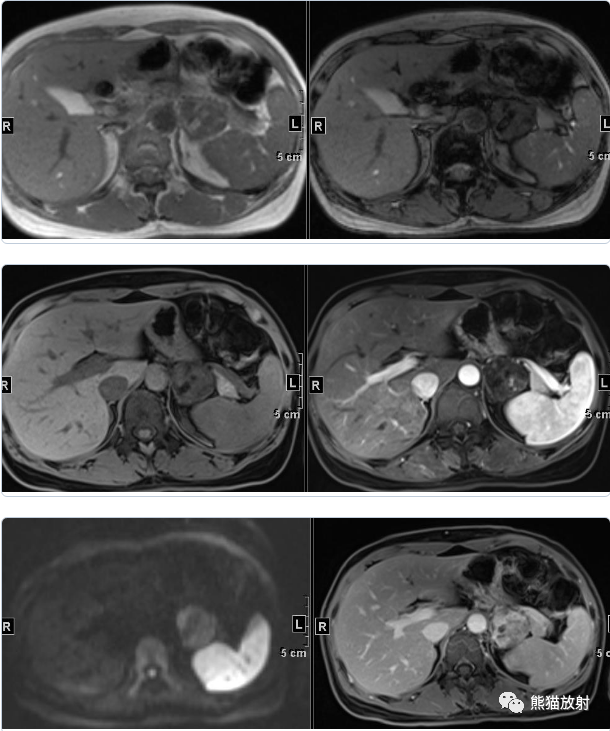

女性,47岁,阵发性头晕、视物模糊4年余,查体发现肾上腺占位。

行肾上腺MRI平扫+增强扫描

⭐️ 左侧肾上腺皮质腺瘤,合并髓样脂肪瘤

? 病灶内含成熟脂肪和脂质成份,在T1反相位和压脂像上局部信号减低。